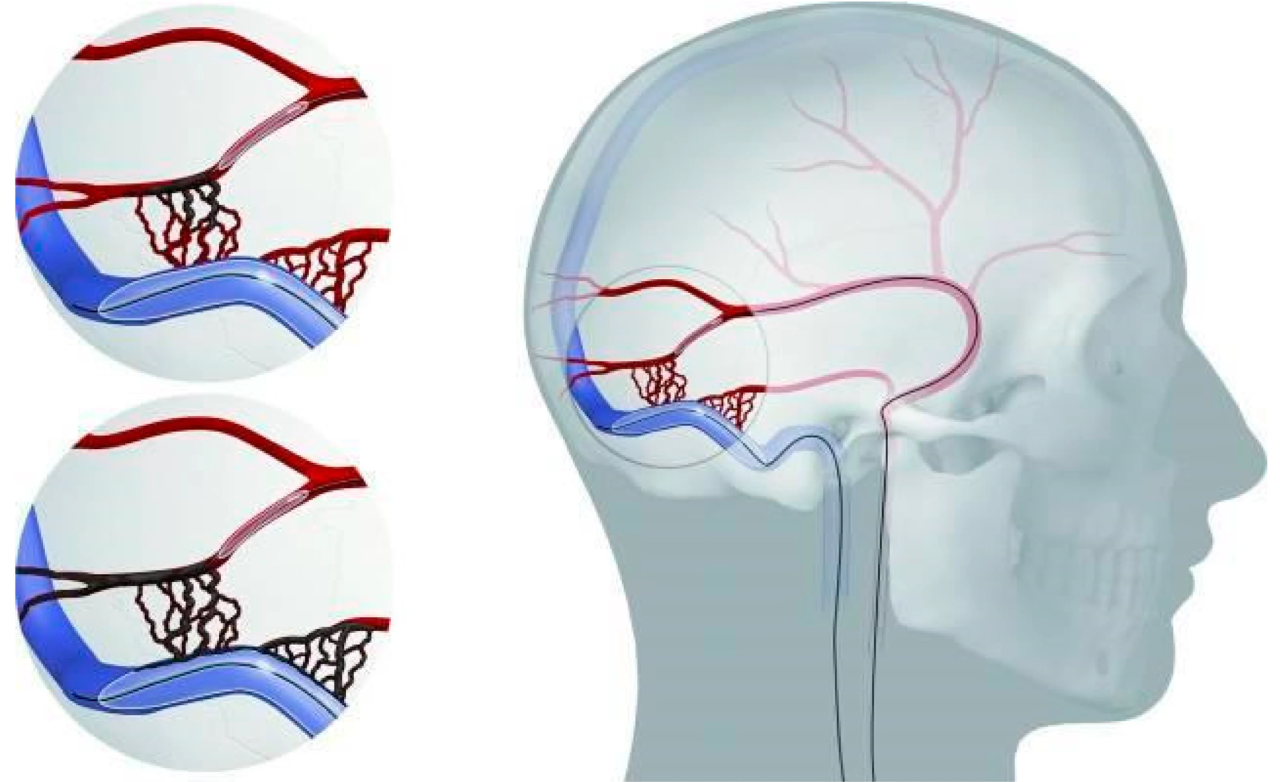

Treats chronic subdural hematoma by blocking the middle meningeal artery, reducing recurrence and supporting faster, safer recovery.